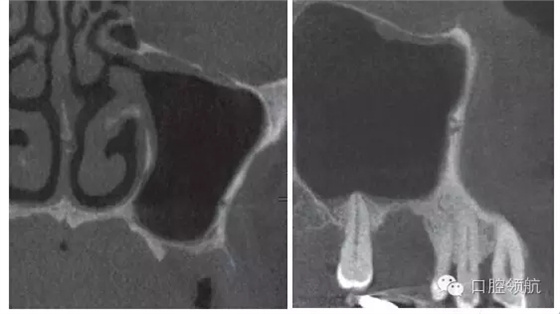

在行植入手術時,手術前一定要根據(jù)CBCT影像確認中鼻道(ostimeatal complex,OMC)的鼻腔形態(tài)(鼻中隔彎曲的狀態(tài),是否是泡狀中鼻甲,下鼻甲是否肥大)和換氣功能是否正常。該病例OMC的換氣功能正常,鼻中隔無彎曲,對右側(cè)上頜竇影響很小。

從矢狀面觀察上頜竇狀態(tài),拔牙后在牙槽窩還沒有消失,垂直提升量不是很多,視野清晰的情況下,選擇經(jīng)牙槽嵴頂入路。

完全去除拔牙窩內(nèi)的肉芽組織,造成上頜竇底的青枝骨折(圖4),植入骨替代材料行上頜竇底提升術。

圖4 確認上頜竇黏膜增厚消失,而且OMC的換氣和排泄功能已改善后,實施經(jīng)牙槽嵴頂入路的上頜竇底提升術。按照常規(guī),造成上頜竇底的青枝骨折,提升上頜竇底。